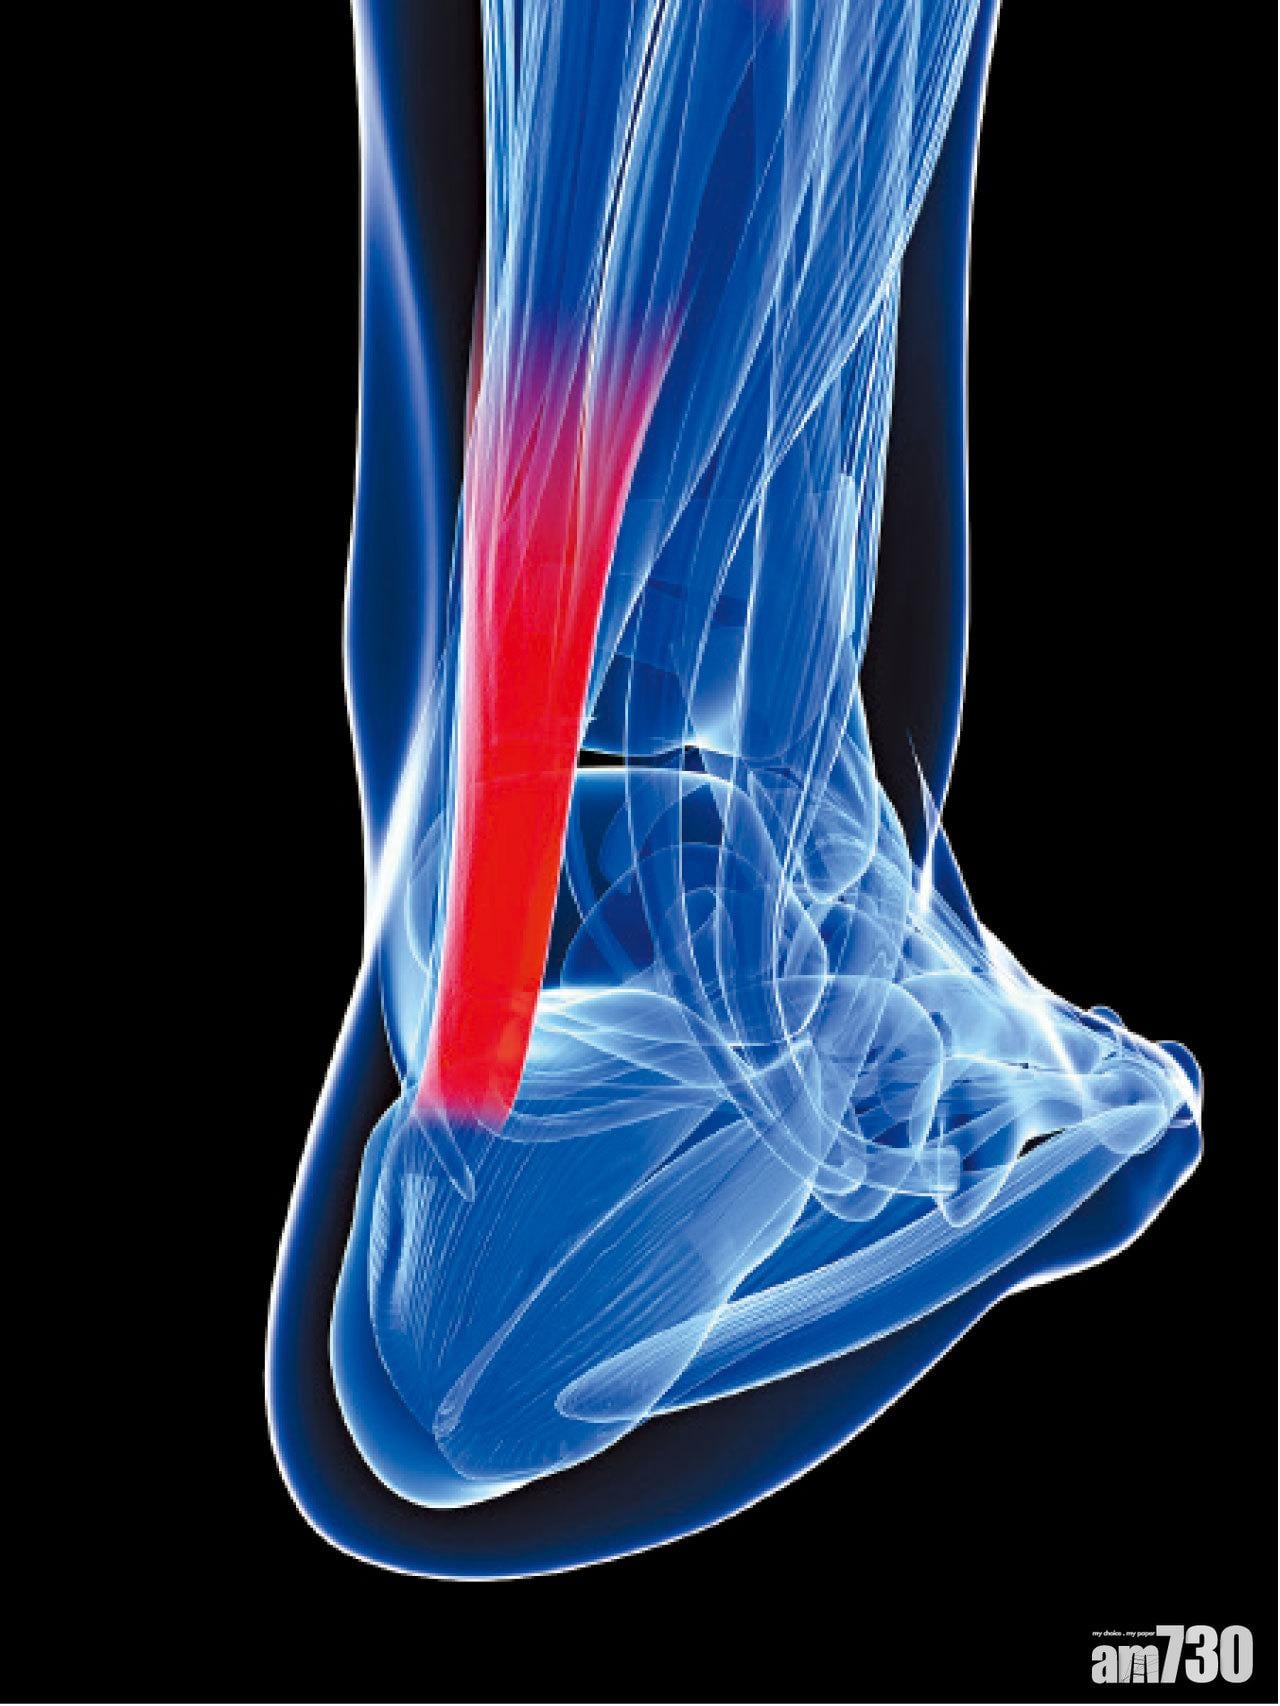

阿基里斯肌腱(Achilles Tendon)是人體內最厚、力量最強壯的一條肌腱,它位於小腿的後方,連接著小腿肌肉和腳跟的位置,主要幫助腳跟關節在走路和運動時向後蹬。阿基里斯肌腱撕裂的患者,年齡通常在20至40歲之間,男較女多。職業運動員如碧咸和劉翔,在高強度的訓練下,亦曾飽受這種傷患的困擾。高危人士也包括平常不做運動,偶然才做一次劇烈運動如羽毛球、足球的人。

受傷的時候,患者一般都在做一些後蹬或跳躍的動作。他們會感覺到或聽到腳跟有「啪」的一聲,彷彿有人踢了他們的後腳跟。他們同時亦會感到劇烈疼痛,腳部後蹬的力量減少和走路困難。有一些病人疼痛的症狀不是那麼明顯,主要是腳部後蹬的力量減少和上落樓梯出現困難,導致有四分一的病人被誤診為肌腱拉傷。